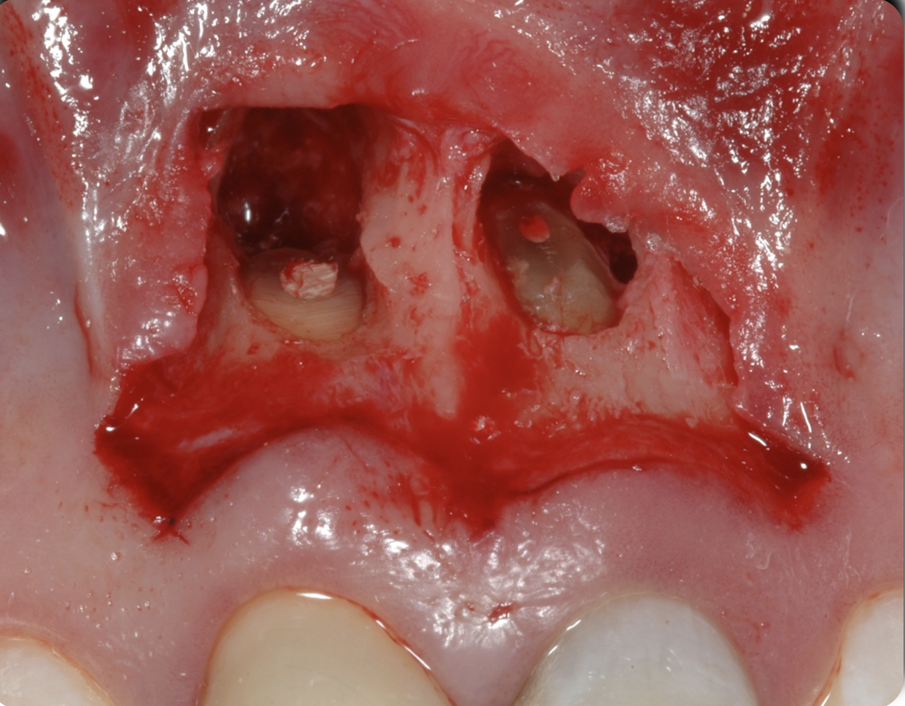

Fig. 5 - Il rapporto tra lesione cariosa e tessuto osseo di sostegno appena sollevato il lembo.

Fig. 6 - La distanza ottenuta tra lesione cariosa e tessuto osseo di circa 3 mm al termine dell’osteo-plastica e ostectomia in prossimità dell’11, con una leggera riduzione in senso buccale della sporgenza della radice.

Figg. 9-11 - Fasi dell’apicectomia eseguita in attesa della completa maturazione dei tessuti parodontali.